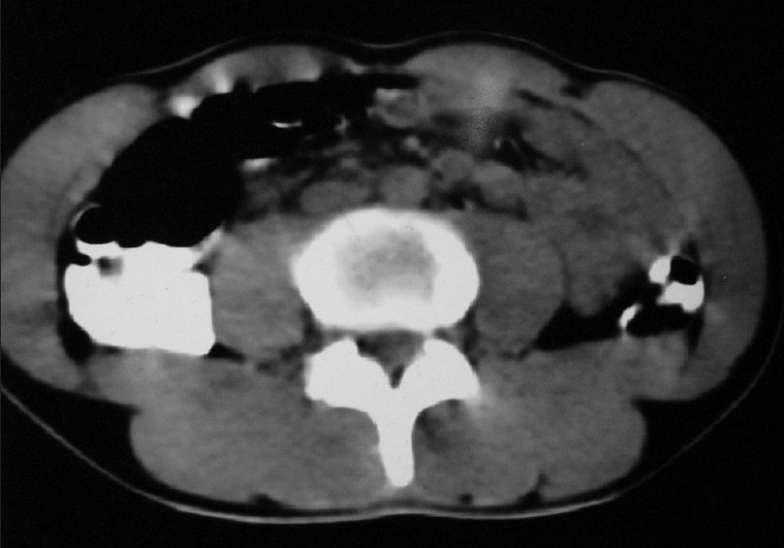

Contrast enhanced Computed tomography (CECT) abdomen showed extrinsic compression of liver by subpleural metastases with multiple para-aortic and peri-aortic lymphadenopathies [Figure 8]. USG (Ultrasonogram) of scrotum was normal. His serum tumor markers were alpha fetoprotein: 4.3 ng/mL beta human chorionic gonadotropin: 39.4 mIU/mL lactate dehydrogenase: 742 U/L.

| Figure 8 CT abdomen (2007) shows multiple para aortic lymphadenopathy